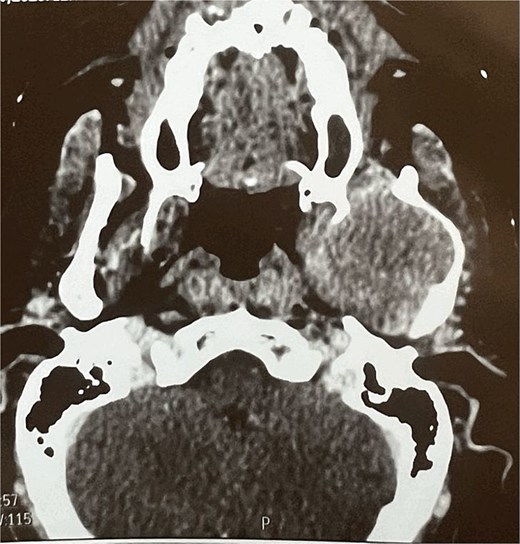

A facial CT scan shows a lesional process occupying the left infratemporal space, which is oval in shape, well-defined, and spontaneously isodense, with a calcified area and fine serpiginous vascular structures. It demonstrates heterogeneous enhancement after contrast injection (Fig. 5).